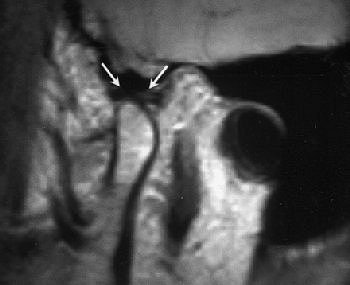

![]() |

Same patient. Above, sagittal MR image obtained in closed-mouth position shows anterosuperior TMJ compartment and disk (arrows) anterior to condyle. Below, sagittal MR image obtained in maximal open-mouth position shows anterosuperior TMJ compartment and disk (arrows) superior to condyle. Emshoff R, Jank S, Bertram S, Rudisch A, Bodner G, "Disk Displacement of the Temporomandibular Joint: Sonography Versus MRI," (AJR 2002; 178: 1557-1562).